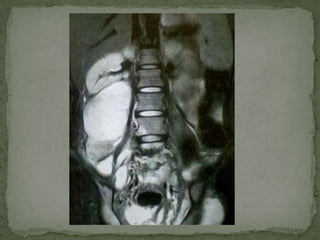

Magnetic resonance imaging

 Ideal means of evaluating SI joints

 Coronal imaging of the SI joints, parallel to the plane of the

sacrum allows direct comparison of one SI joint to the other

 Erosions

 Destruction

 Abscess

 Associated disseminated tuberculous osteomyelitis